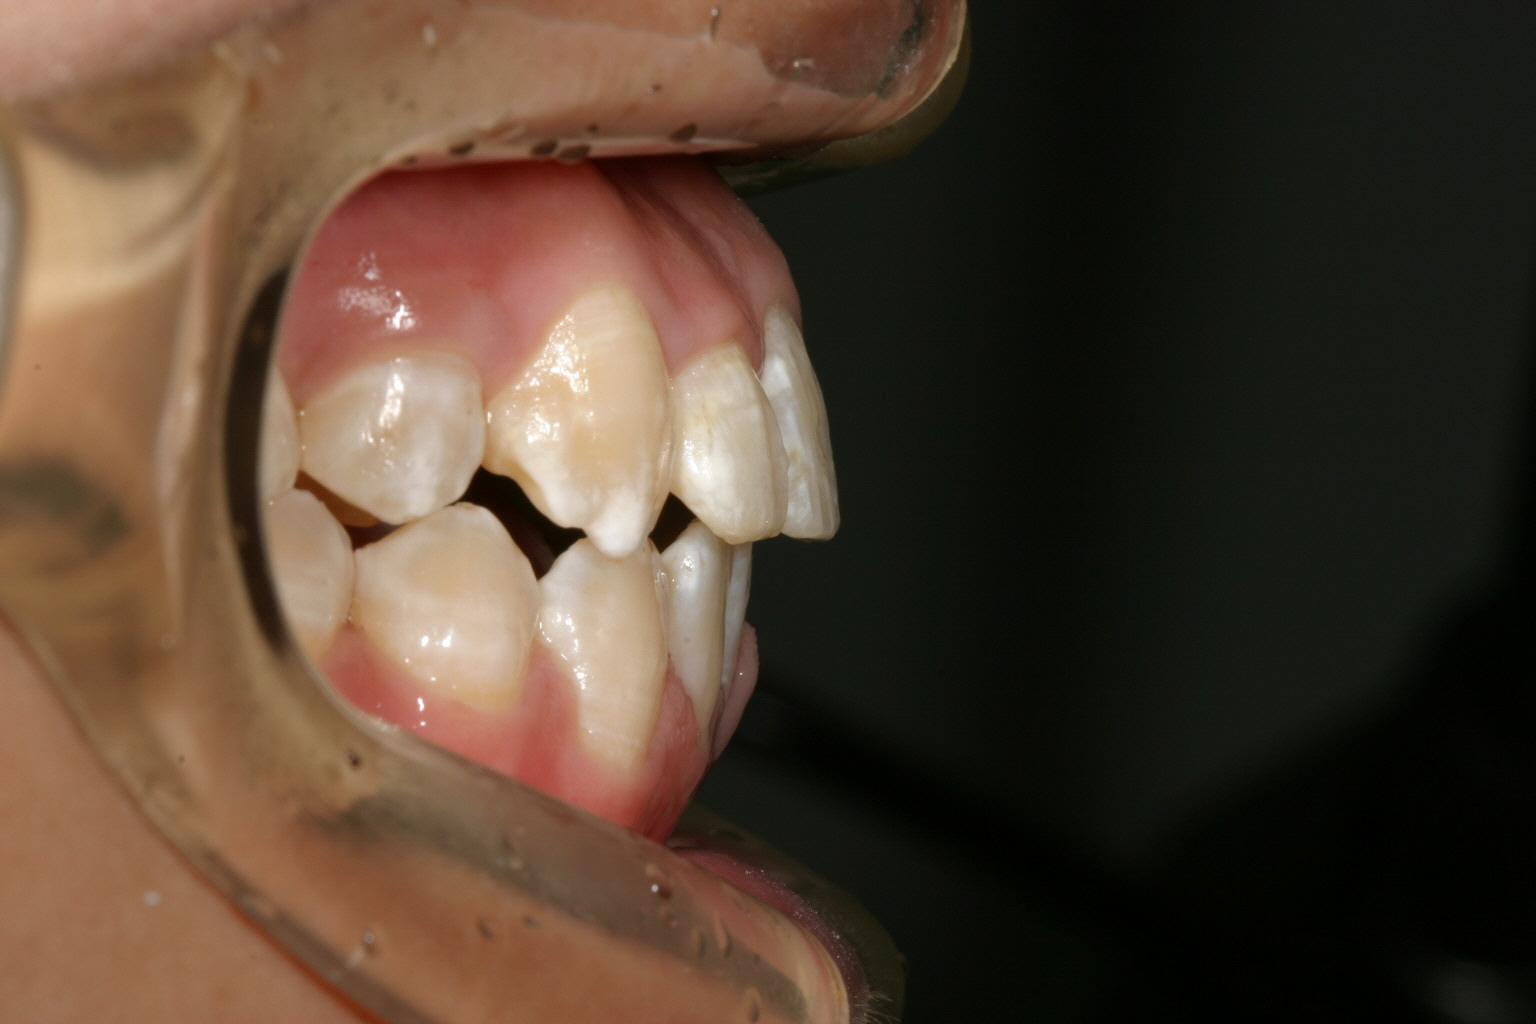

右上の犬歯が飛び出しているのが気になります。

オーバージェットが少なく切端咬合になっています。

マルチループワイヤー使用で3ヵ月です。 もう殆ど犬歯の飛び出し改善してます。